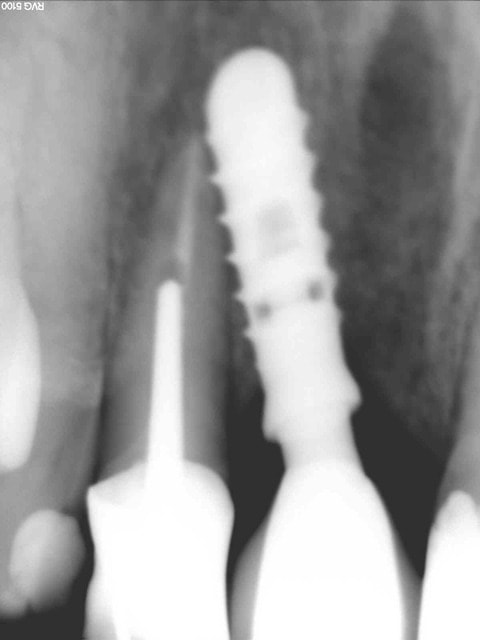

Céramik comme promis Ma réponse en image 2ans après

2 Pano qui a déclenché tous ces gentils commentaires

6 Rx aujourd'hui